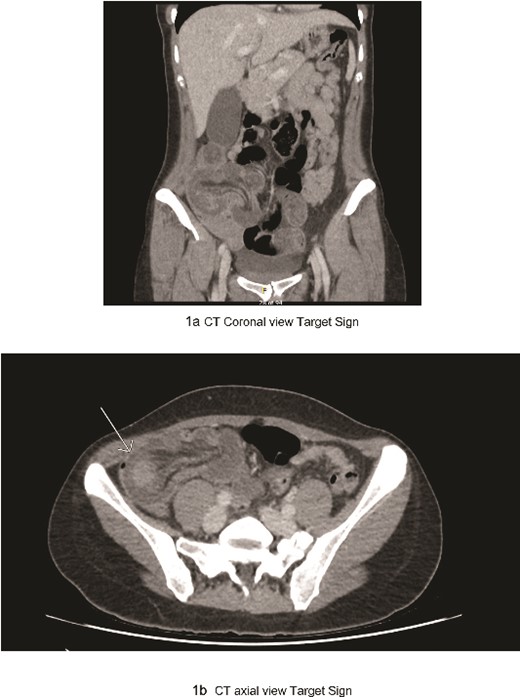

The patient’s significant familial history of ovarian and breast cancers immediately prompted considerations of underlying malignancy. Initial laboratory tests indicated leucocytosis and elevated inflammatory markers, while radiologic assessment through abdominal and pelvic computed tomography scans revealed ileocolic intussusception (Fig. 1a and b) and an ovarian teratoma, raising immediate concerns for a malignant aetiology given the rare presentation in an adult.

(a) CT coronal view target sign; (b) CT axial view target sign.